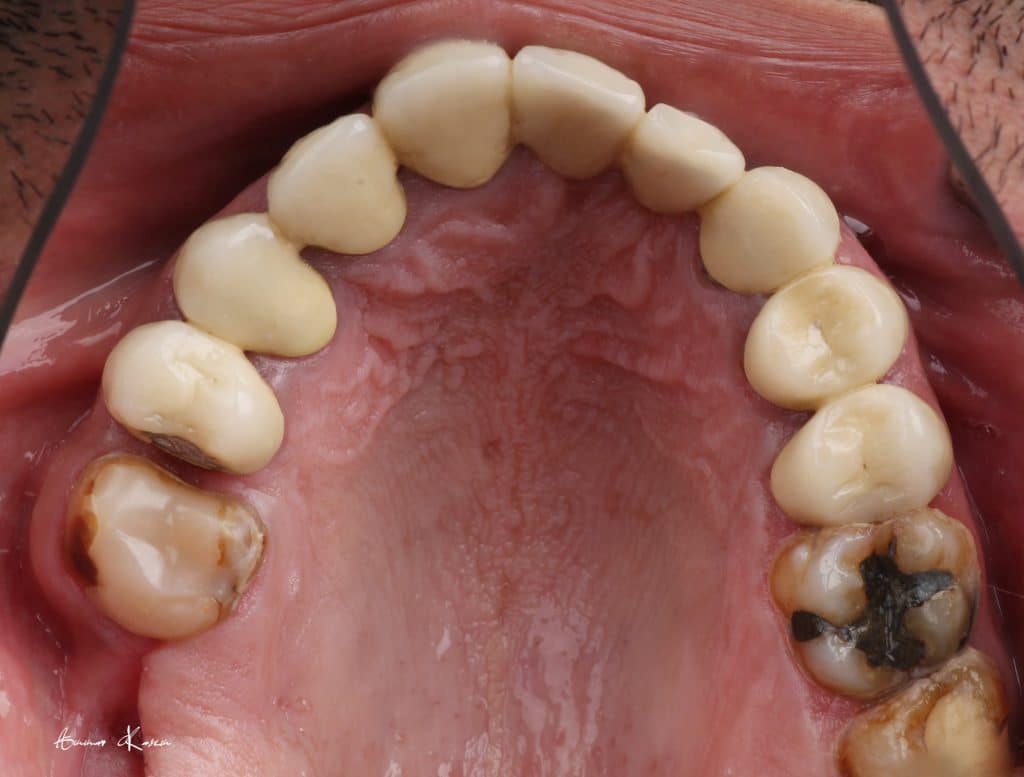

35 years old male patient having old PFM restorations

The patient was normally class I occlusion type ( according to old photos and cephalometric analysis) till he received this defective restorations 10 years ago

1- Removal of old restorations